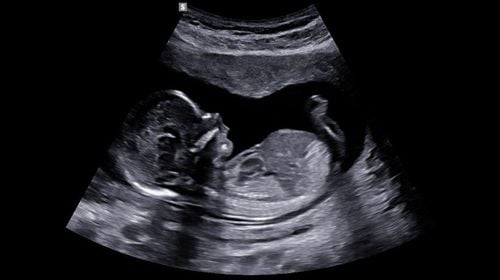

Các dị tật bẩm sinh đối với thai nhi luôn là ác mộng với các bà mẹ, bất cứ thai nhi nào đều có thể mắc các dị tật bẩm sinh ở các mức độ khác nhau, do đó việc phát hiện sớm các dị tật thai nhi là hết sức quan trọng để có biện pháp xử lý và theo dõi hợp lý. Hiện nay siêu âm một trong những phương pháp hiệu quả nhất, an toàn nhất, được áp dụng nhiều nhất để phát hiện các dị tật thai nhi, thậm chí từ rất sớm.

• Siêu âm dị tật thai nhi là phương pháp rất an toàn, hiệu quả, dễ thực hiện với chi phí hợp lý để chẩn đoán, theo dõi thai kỳ, cũng như phát hiện, theo dõi các dị tật thai nhi ở các giai đoạn khác nhau, ngay từ khi rất sớm, siêu âm thai với các điều kiện lý tưởng có thể chẩn đoán chính xác tới 85% đến 90% các trường hợp dị tật thai nhi.

Ở trong giai đoạn từ 12 tuần tuổi, bé đã phát triển tương đối đầy đủ về mặt hình thái và có những phản xạ như gập duỗi thân mình, duỗi các chi... Vì thế đây là một trong 03 mốc siêu âm dị tật quan trọng được các chuyên gia khuyến cáo cần thực hiện. Trong lần siêu âm này các bác sĩ sẽ đặc biệt kiểm tra và sàng lọc các dị tật sớm về não, mặt, tim, tiêu hóa, tiết niệu, tứ chi và toàn bộ hình thể cũng như cung cấp các thông tin cơ bản của thai nhi, khẳng định thai nhi còn sống hay không? Xem thai nhi đã ở đúng vị trí chưa? Có bao nhiêu thai? Tính tuổi thai chính xác dựa vào chiều dài đầu mông.

Bên cạnh đó, siêu âm thai trong thời gian 12 tuần là thời điểm vàng để phát hiện một số các bất thường thai nhi nếu có như: Hội chứng Down, Hội chứng Edward... Do em bé trong giai đoạn này vẫn còn khá nhỏ nên hệ thống máy siêu âm 4D cao cấp như GE Voluson E10 sẽ đóng vai trò vô cùng quan trọng giúp các bác sĩ tại Vinmec phát hiện đến hơn 95% dị tật trong giai đoạn này. Được trang bị các công nghệ mới nhất, GE Voluson E10 cho phép tăng cường chất lượng hình ảnh và độ xuyên thấu mang lại hình ảnh có độ phân giải cao vượt trội và thao tác dễ dàng.

Ở thời điểm này, thai nhi cơ bản đã phát triển đầy đủ các cơ quan bộ phận cơ thể, lượng nước ối cũng nhiều lên cho phép quan sát tốt hình thái của thai nhi. Đây là thời điểm siêu âm tiêu chuẩn để đánh giá toàn bộ thai nhi.